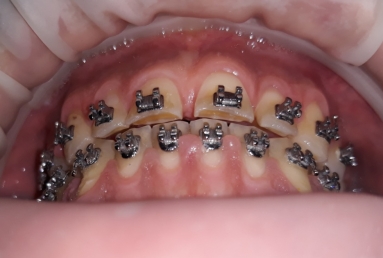

Then fixed orthodontic treatment is set for almost 2 years, so moving the teeth a new more favorable position is obtained to create space for veneers. After wax up a mock up is done for provisional veneers and the new occlusion is tested.